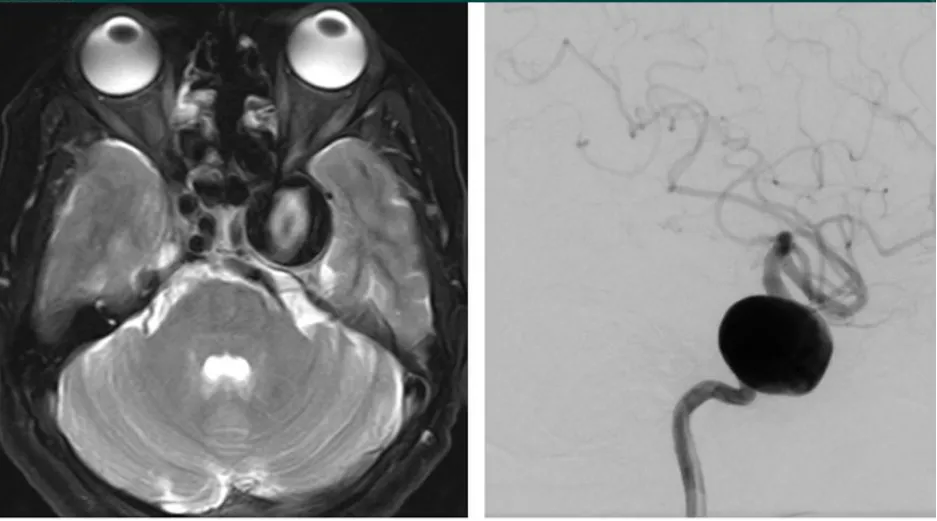

圖:海綿竇區(qū)頸內(nèi)動脈瘤